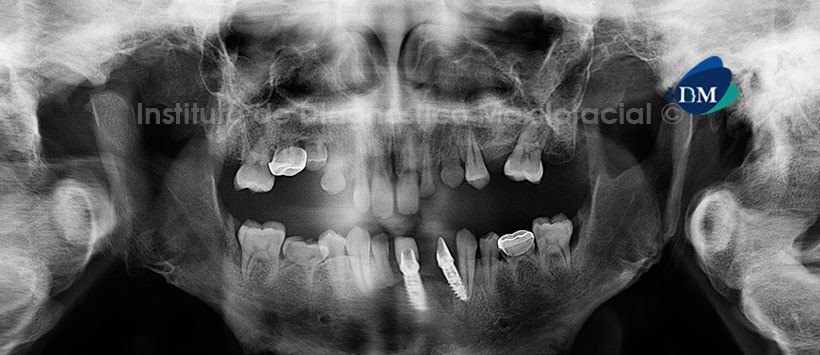

A la evaluación de la radiografía panorámica (Figura1) observamos aumento de la densidad ósea generalizada acompañada de deformidad de las estructuras óseas comprometidas (maxilar superior, mandíbula, base craneal, vértebras cervicales etc). Así mismo apreciamos múltiples agenesias dentarias como también persistencia en boca de muchas piezas deciduas.

Al estudio mediante tomografía computarizada de haz cónico (CBCT), mediante cortes axiales (Figura 2) y coronales (Figura 3) se evidencia la alteración del patrón de trabeculado ósea, que ocasiona la deformación de los mismos, además de la presencia de implantes dentales en el sector ántero inferior.

Las imágenes radiográficas características de la última etapa de la enfermedad, se relacionan con una disposición irregular del hueso recién formado, que produce un patrón de parches radiopacos denominado “copos de algodón“. En los maxilares, este patrón se asocia con hipercementosis radicular, pérdida de la lámina dura, pérdida del espacio del ligamento periodontal y resorción de raíces.